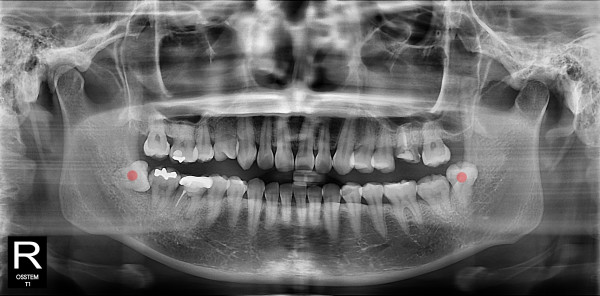

사랑니발치 20대/여성

ae27575af29d49719312fde5a1f0cca6_1764402427_3314.jpg